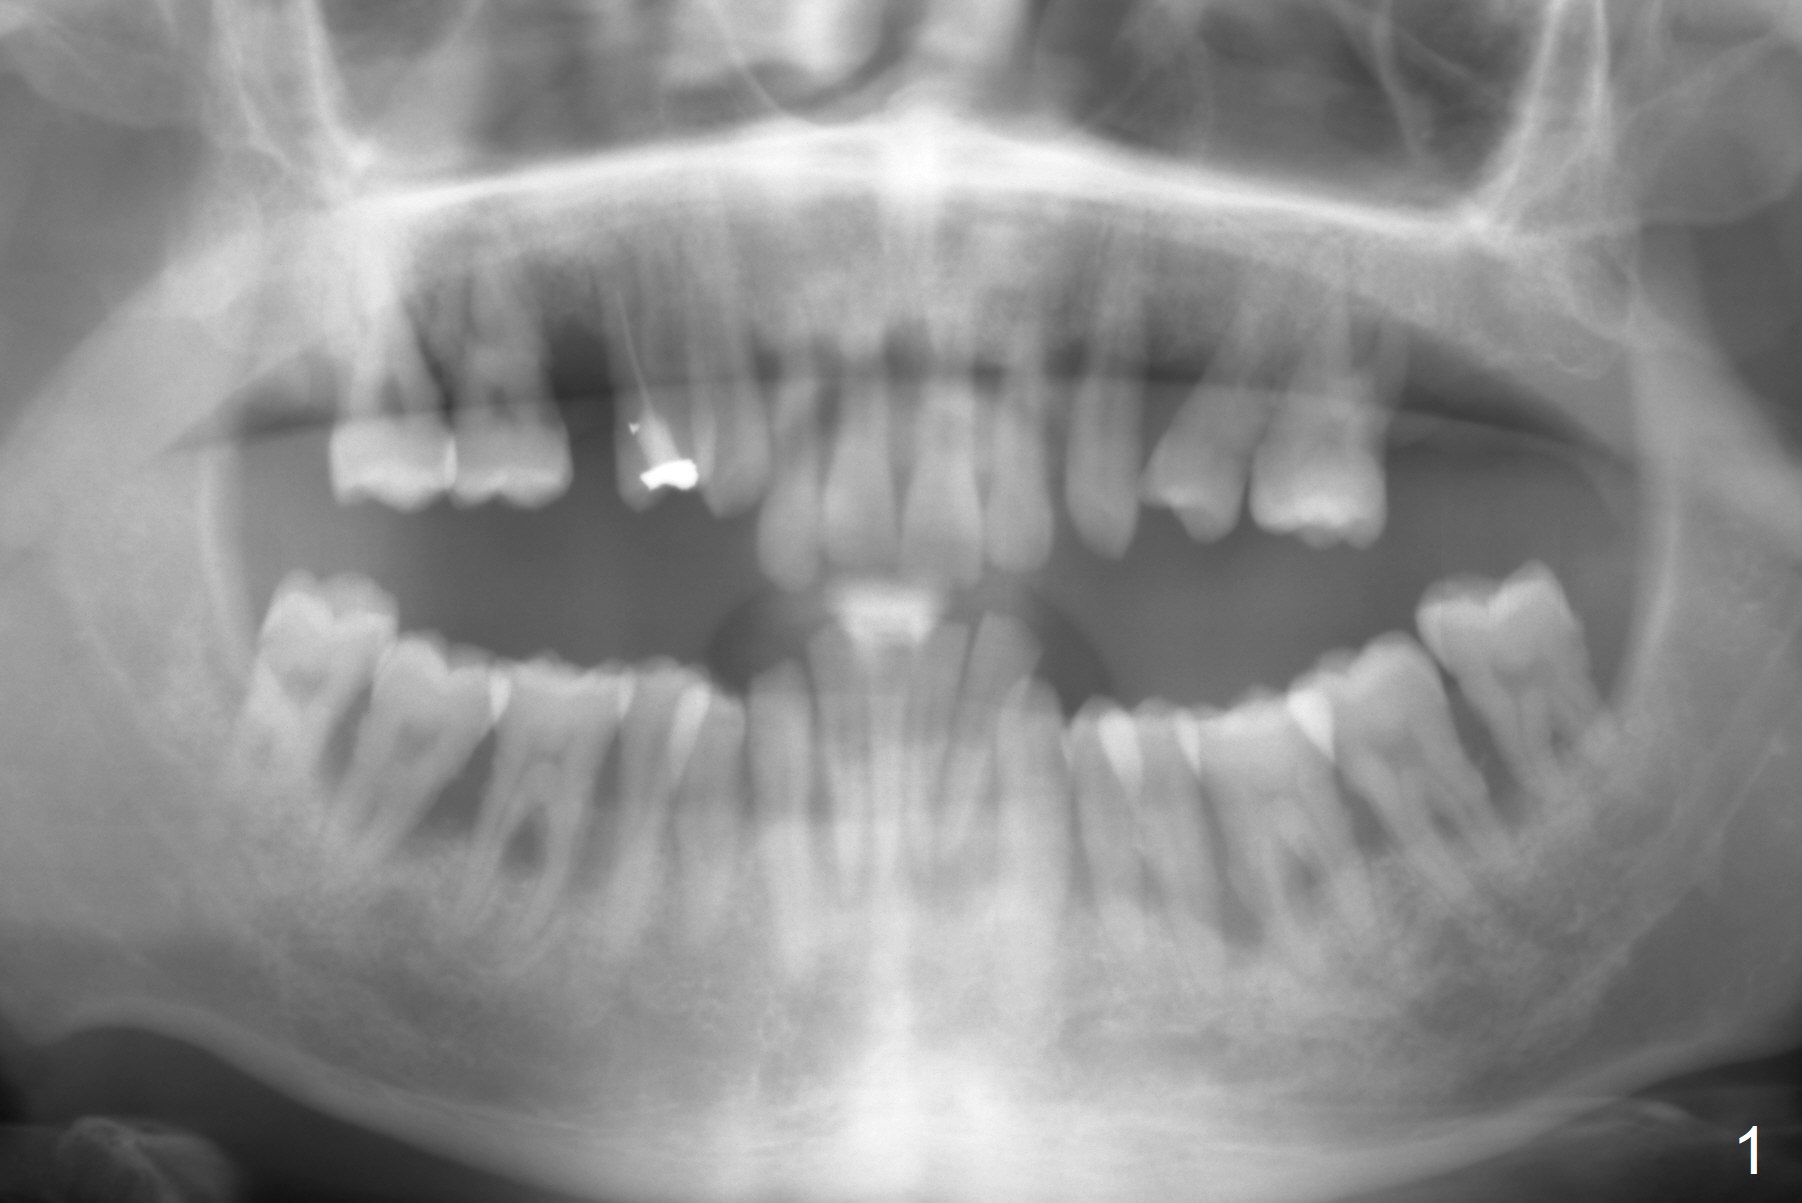

A 36-year-old man has generalized periodontitis (Fig.1). The mobile lower incisors will be extracted for immediate provisional FPD (Fig.2). The initial depth will be 16 mm. Get ready 2 of 1.2 mm drill. If the affected teeth are well aligned, take Alginate impression for surgical stent. In fact the patient has taken CT, which shows narrow 2-piece implants appropriate for the sites.